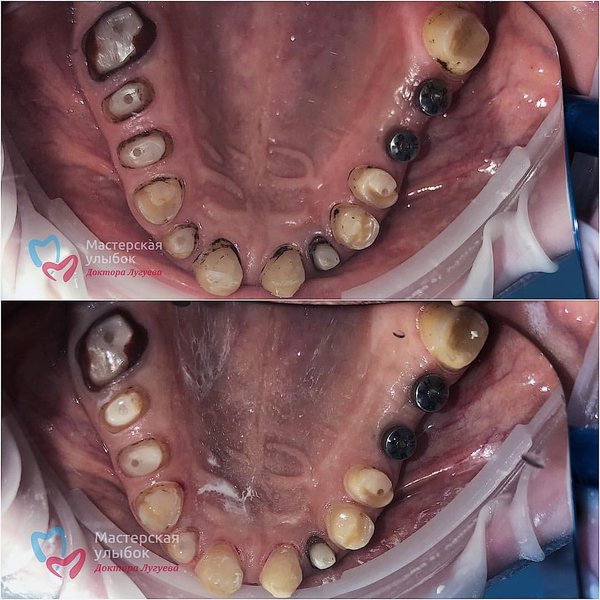

С вас лайк ️. . Листаем фото в карусели. . Позвонила к нам как-то в клинику пациентка, и говорит я к вам на консультацию а так же хочу спасти свой зубик, но спасать было уже нечего, зуб был сильно разрушен, и его пришлось удалять. Поэтому не затягивает с зубами и приходите вовремя их лечить! А пациента мы будем готовить к следующему этапу лечения ️ . Работа врача: Аскерхана Мирзихановича